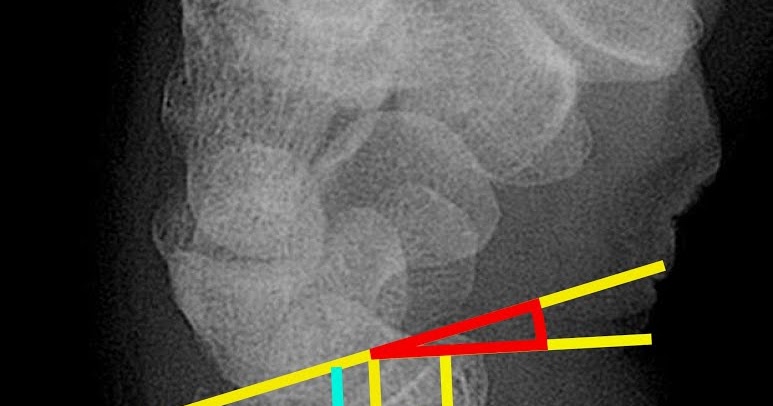

Torus Fracture-Radius - Sumer's Radiology Blog

Torus Fracture-Radius - Sumer's Radiology Blog sumerdoc.blogspot.com

torus fracture radius radiology bone

Fracture torus wikidoc plain ray. Torus fracture – radiology cases. Torus fracture radius